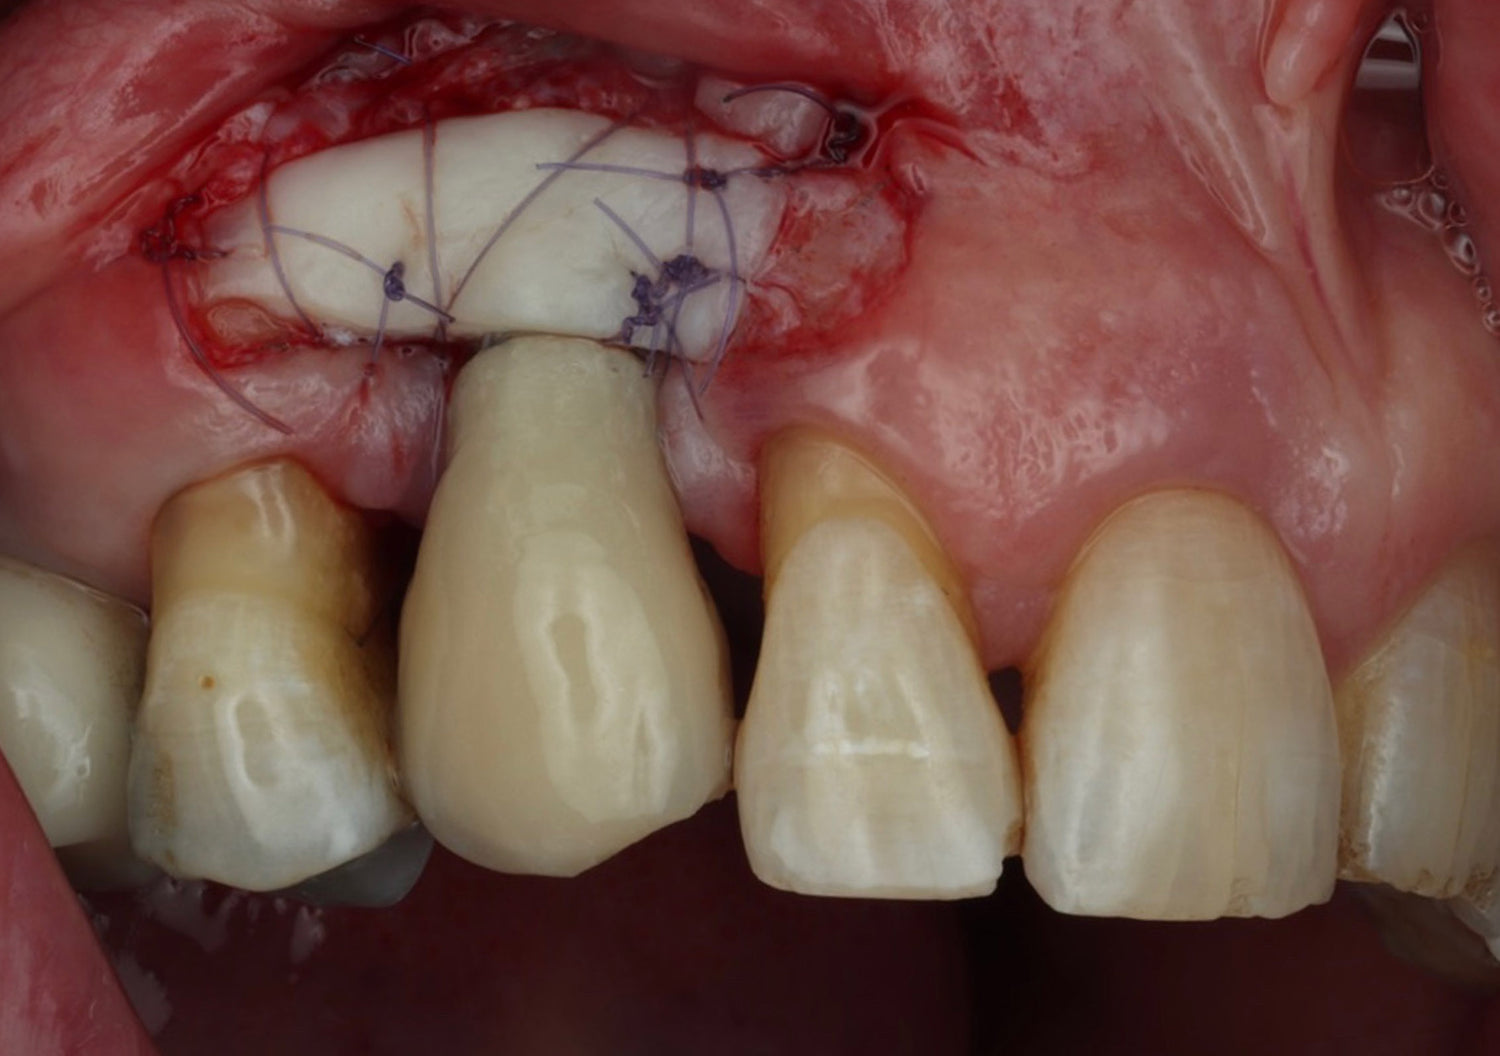

- Develop a thorough understanding of the critical soft tissue parameters that determine implant success

- Gain practical experience in soft tissue management and augmentation techniques for optimal peri-implant outcomes

Soft tissue hands-on techniques:

- Free gingival graft

- Vestibuloplasty

- Rotated palatal pedicle